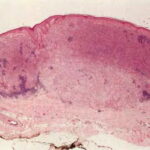

Common Tumorigenic Melanoma Including Nodular Melanoma Nodular melanoma by definition contains only tumorigenic vertical growth (sometimes associated with a precursor) and, because of this, has a poorer prognosis on the average than superficial spreading melanoma. However, when other risk factors such as thickness are controlled, the prognosis of nodular melanoma is not worse than that of other forms of melanoma . Nodular melanomas occur in slightly older patients than the common superficial spreading melanoma and are relatively more frequent in men . A nodular melanoma starts as an elevated, variably pigmented papule that increases in size quite rapidly to become a nodule and often undergoes ulceration. Certain rare primary dermal melanomas comprised of cytologically malignant melanocytes and lacking an in situ |

component may be considered also in this category . The ABCD criteria reviewed earlier do not apply to nodular melanomas, which often present clinically as quite small, symmetric, and well-circumscribed papules or nodules . These may be conspicuously pigmented, oligomelanotic, or even amelanotic. The tumorigenic nodule that may develop in nodular melanoma does not differ clinically or histologically from that which may occur in relation to a preexisting nontumorigenic melanoma. Indeed, nodular melanomas may represent examples of telescoped tumor progression in which the antecedent radial phase has been so short lived as to be unapparent . The clinical importance of the nodular subtype has been emphasized recently; these lesions are more likely to present at a biologically advanced stage despite a comparatively short clinical history . The mutation profile of nodular melanoma is closer to that of superficial spreading melanoma than to the other subtypes, in that BRAF or NRAS are commonly mutated . |

In some instances, it may be difficult to recognize a highly undifferentiated melanoma as such. The specific identification of a tumor as melanoma depends on the identification of melanin or on appropriate immunohistochemical reactivity in an appropriate setting. The amount of melanin present varies greatly in melanomas. In some tumors, considerable melanin is found not only within the tumor cells, but also within melanophages located in the stroma. In others, there may be no evidence of melanin in hematoxylin-eosin stains. However, a Fontana-Masson silver stain usually reveals at least a few cells containing melanin . Some melanomas are completely devoid of pigment (amelanotic melanoma). Although amelanotic melanomas tend to be aggressive lesions, the prognosis is not different from that of pigmented melanomas when other staging and microstaging attributes are taken into consideration . If appropriate tissue is available, the DOPA reaction |